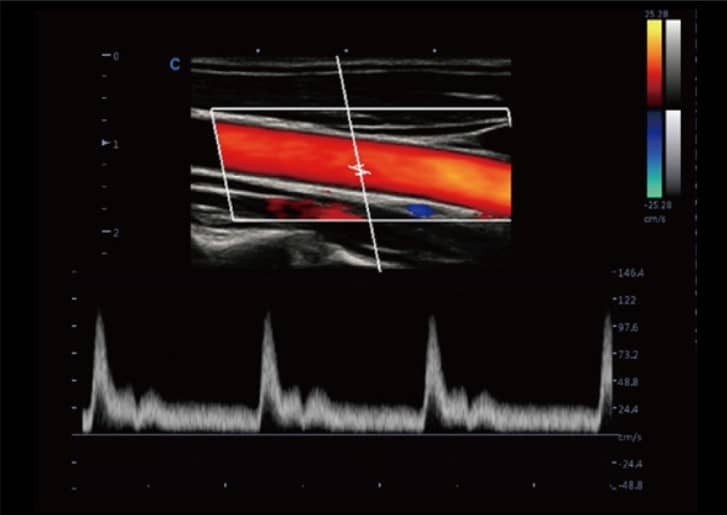

- Doppler Thông Minh: Tự động điều chỉnh hướng ROI và PFR, đem lại hiệu quả và dễ dàng đo lường hơn, tập trung vào bệnh nhân một cách tối ưu.

- SonoColor và SonoContrast: Cung cấp phân tích dòng định lượng và độ nhạy cao hơn, thích ứng với mọi loại đầu dò.